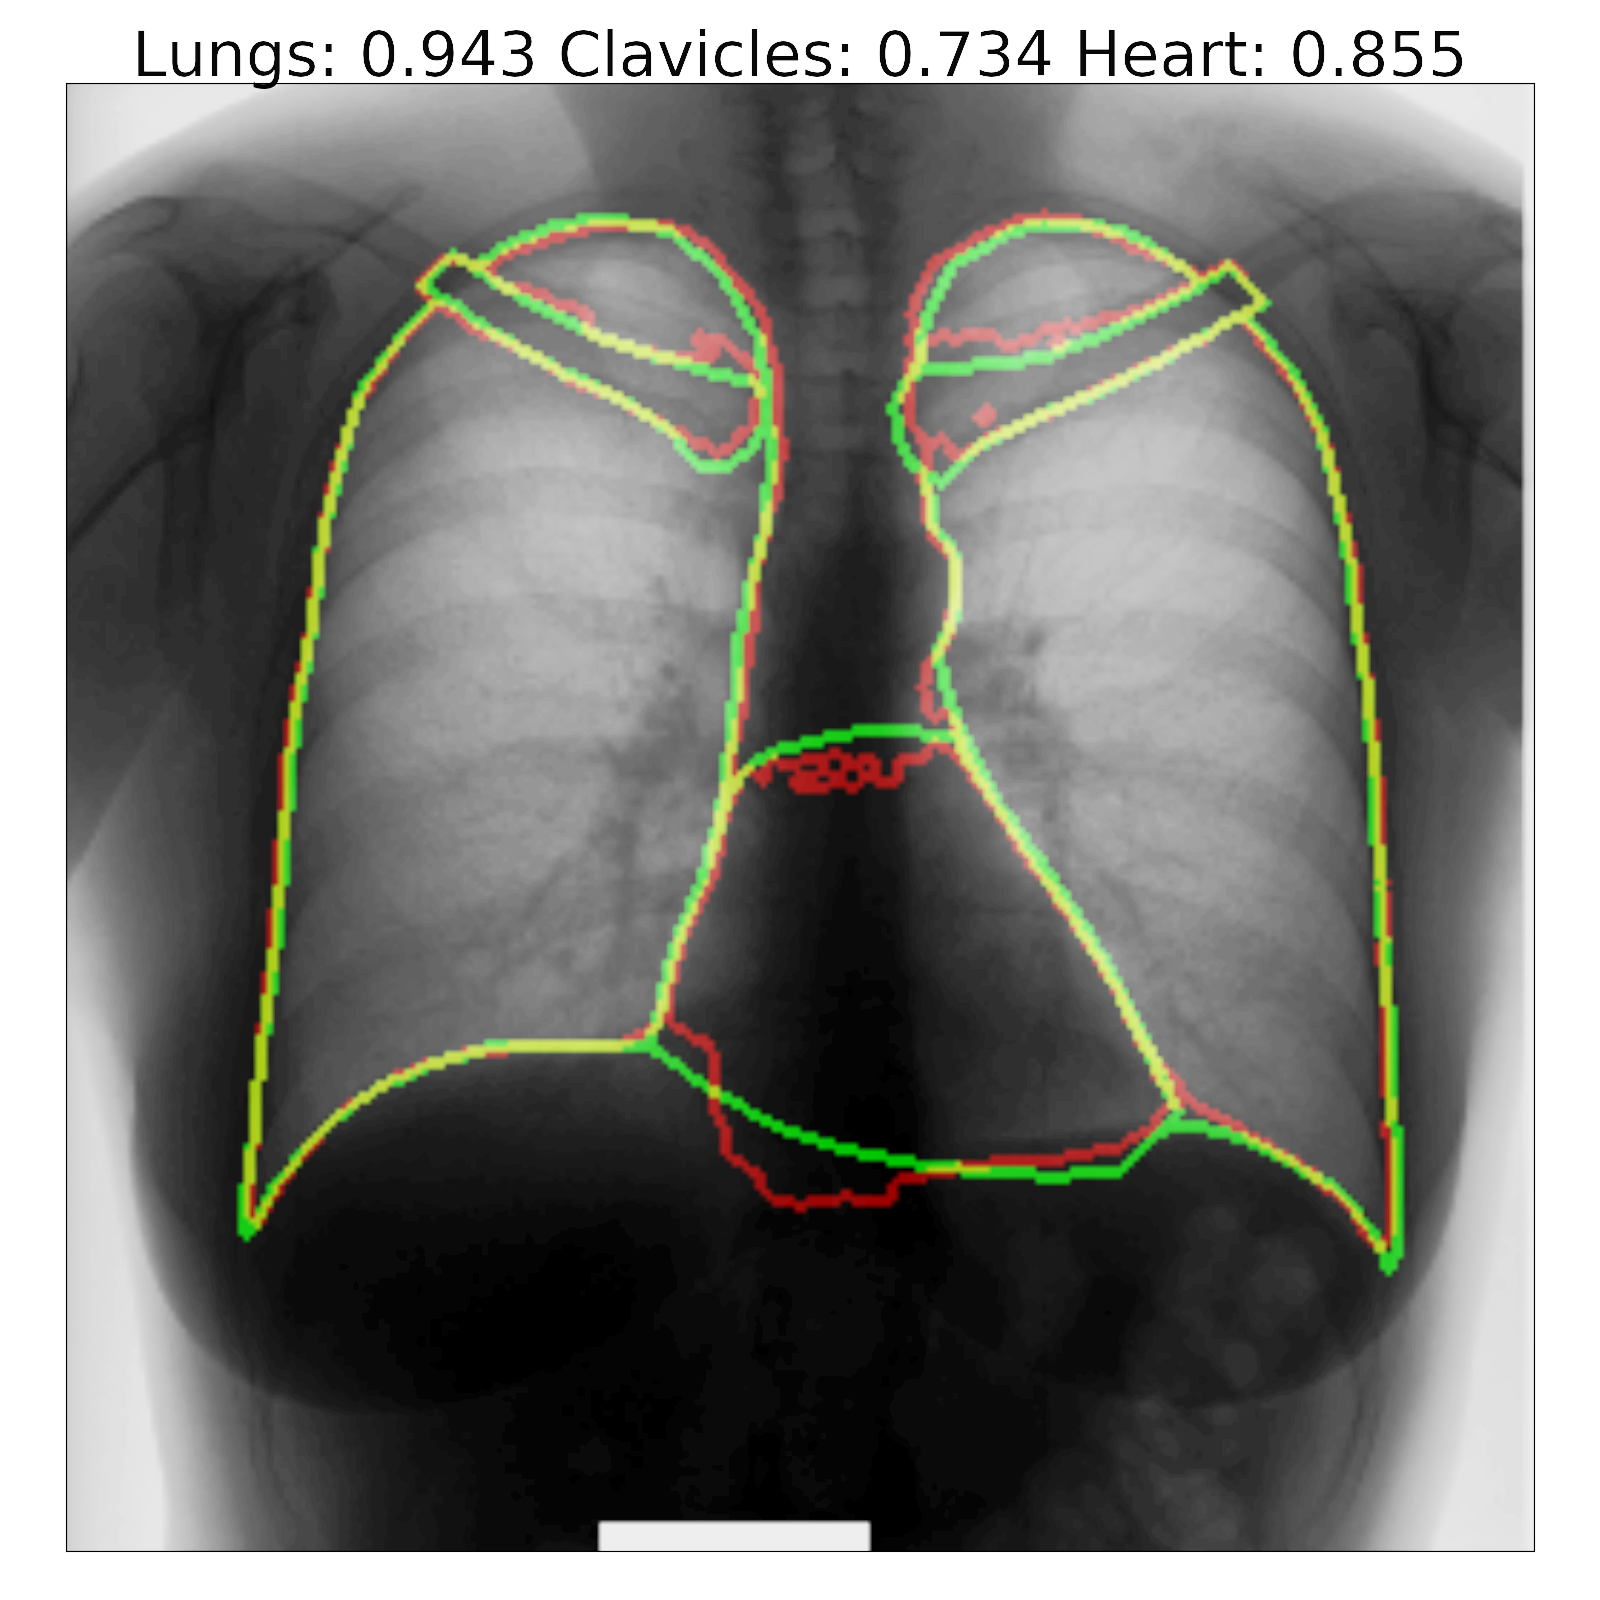

Figure 7: Segmentation results and corresponding Jaccard scores on some images for U-Net (top row) and proposed InvertedNet with ELUs (bottom row). The contour of the ground-truth is shown in green, segmentation result of the algorithm in red and overlap of two contours in yellow.

Fig. 7 shows a few examples of the algorithm results for both successful and failed cases for U-Net (top) and the InvertedNet  trained with the ELU and loss function based on the Dice coefficient. The white boxes show Jaccard scores for lungs, clavicles and heart. To extract the shape contours of the segmentation and ground-truth, we used a morphological outline extraction algorithm on both segmentation result and reference masks. The contour of the ground-truth is shown in green, the segmentation result of the algorithm in red and the overlap of two contours in yellow colors.